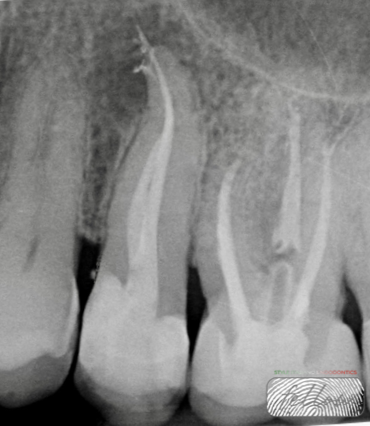

Fig. 5

Root canal obturation was performed for each canal using a bioceramic sealer with a single-cone technique.

Radiographs at 6 months showed the initial signs of healing.

Fig. 9

At 11 months, radiographs confirmed progressive and complete periapical healing. The patient will continue to be monitored with yearly follow-ups.